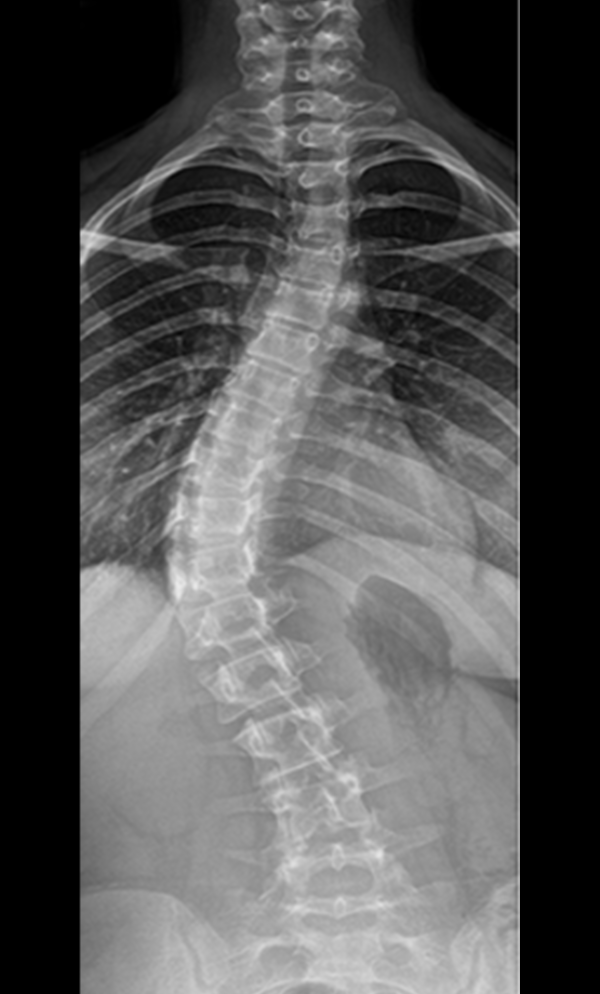

Scoliosis is a common condition characterized by a sideways curvature of the spine, often emerging during puberty. While its origins can vary, most cases are mild. However, without proper attention, severe deformities may lead to significant functional disabilities, impacting lung function and overall well-being.

Gallery : Before - After

After

Before